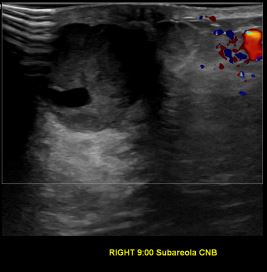

상기환자는 외부 건강검진 이상소견으로  정밀검사위해 내원하신 50대 초반

여성분으로 의심스러운 우측유방혹 조직검사 시행해 유방암으로 진단되었습니다